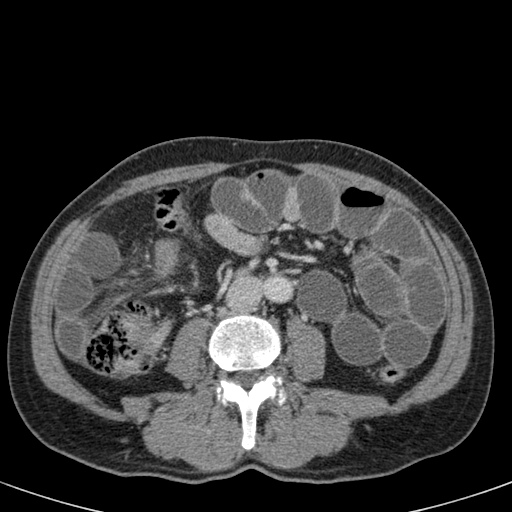

Đây là một bệnh nhân bị tắc ruột non.

Cuộn qua các hình ảnh.

Bạn có thể tìm thấy quai kín và nguyên nhân gây ra nó không?

Khi tiếp nhận bệnh nhân tại phòng cấp cứu với biểu hiện nghi ngờ tắc ruột non (SBO), điều quan trọng nhất chúng ta cần làm, ngoài việc chẩn đoán xác định, là xác định sự hiện diện hay vắng mặt của tình trạng thắt nghẹt.

CT là phương pháp chẩn đoán hình ảnh được lựa chọn trong đánh giá bệnh nhân nghi ngờ tắc ruột non.

Hình ảnh CT của tắc ruột non dạng quai kín phụ thuộc vào hai yếu tố:

- chiều dài đoạn ruột tạo thành quai kín

- hướng của quai ruột so với mặt phẳng tạo ảnh

Nếu quai kín ngắn và nằm trong mặt phẳng tạo ảnh, chúng ta sẽ thấy quai ruột hình chữ U hoặc chữ C.